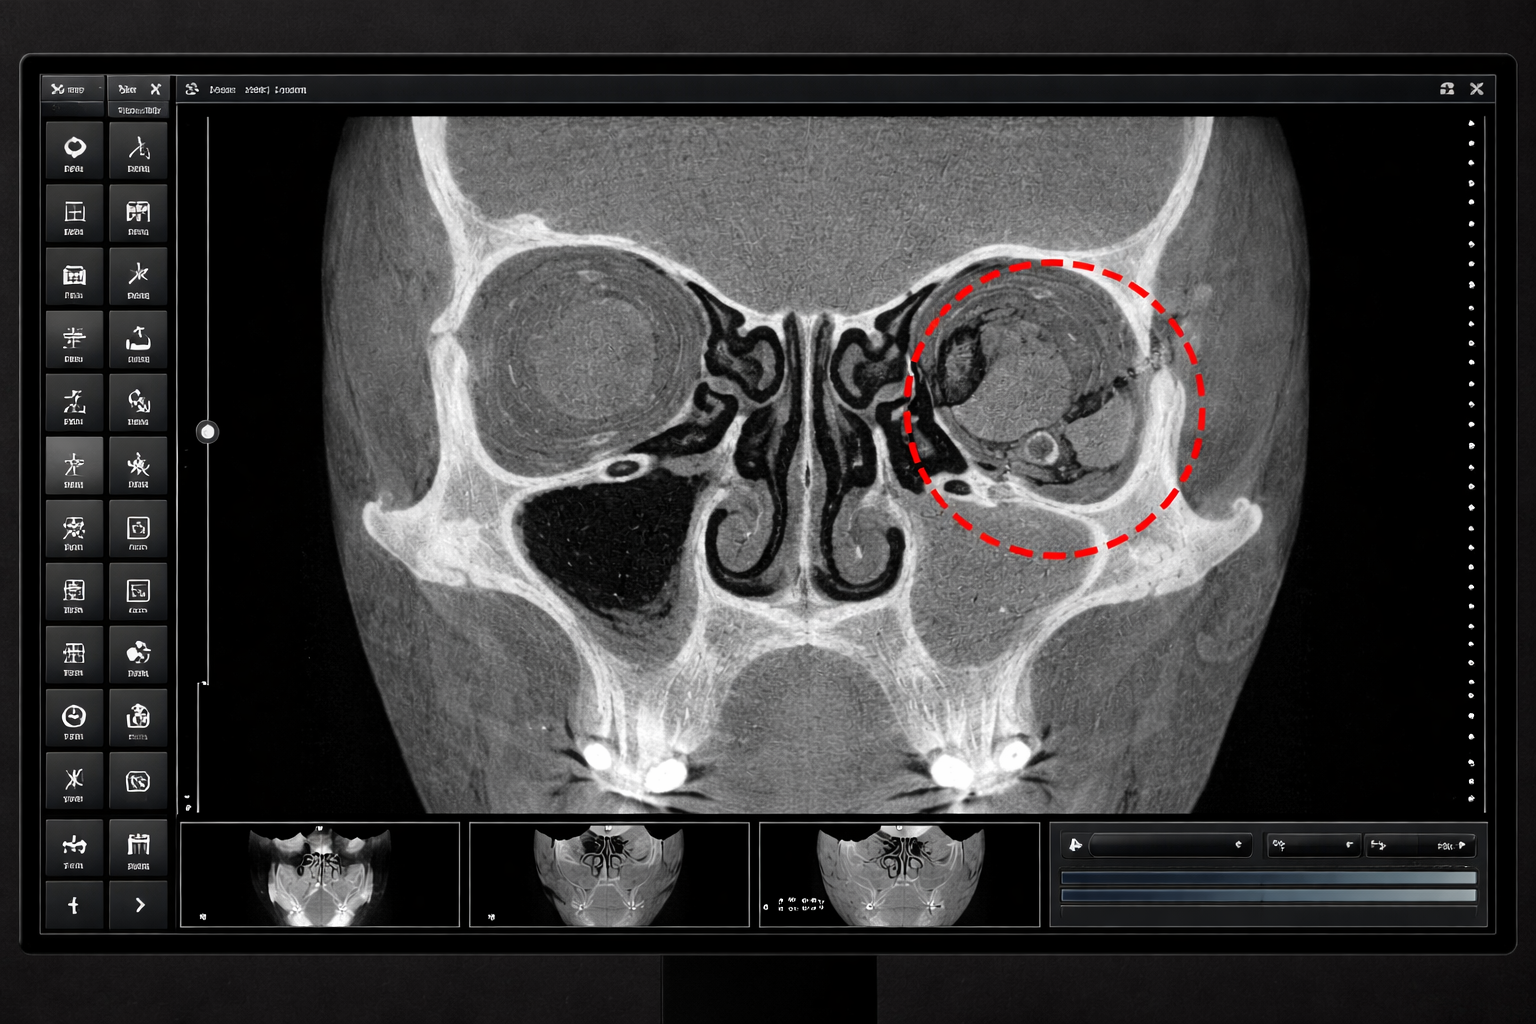

Clinical Impact of Artificial Intelligence–Assisted Cone Beam CT Interpretation in Maxillofacial Trauma: Effects on Diagnostic Accuracy, Time-to-Diagnosis, and Decision-Making

Yildirim A., Hertach R., and Yildirim V.

This study demonstrates that AI-assisted interpretation of DVT images enables near-perfect detection of maxillofacial fractures while significantly reducing diagnostic time. The benefit is most pronounced for junior surgeons, highlighting the clinical value of AI as a decision-support tool in emergency maxillofacial trauma care.

Original Rearch Article– Dec 31, 2025

External Multicenter Validation of an Artificial Intelligence System for Cone-Beam CT–Based Detection of Maxillofacial Fractures: Robustness Across a Tertiary Facial Trauma Clinic and an Independent Maxillofacial Practice

This multicenter study externally validated an artificial intelligence (AI) system for detecting maxillofacial fractures on cone-beam CT (DVT) scans. The AI demonstrated high sensitivity, specificity, and overall accuracy across both a tertiary trauma clinic in Zurich and an independent maxillofacial practice in Munich. Performance was comparable to senior clinicians, significantly faster than human interpretation, and robust across different clinical settings.